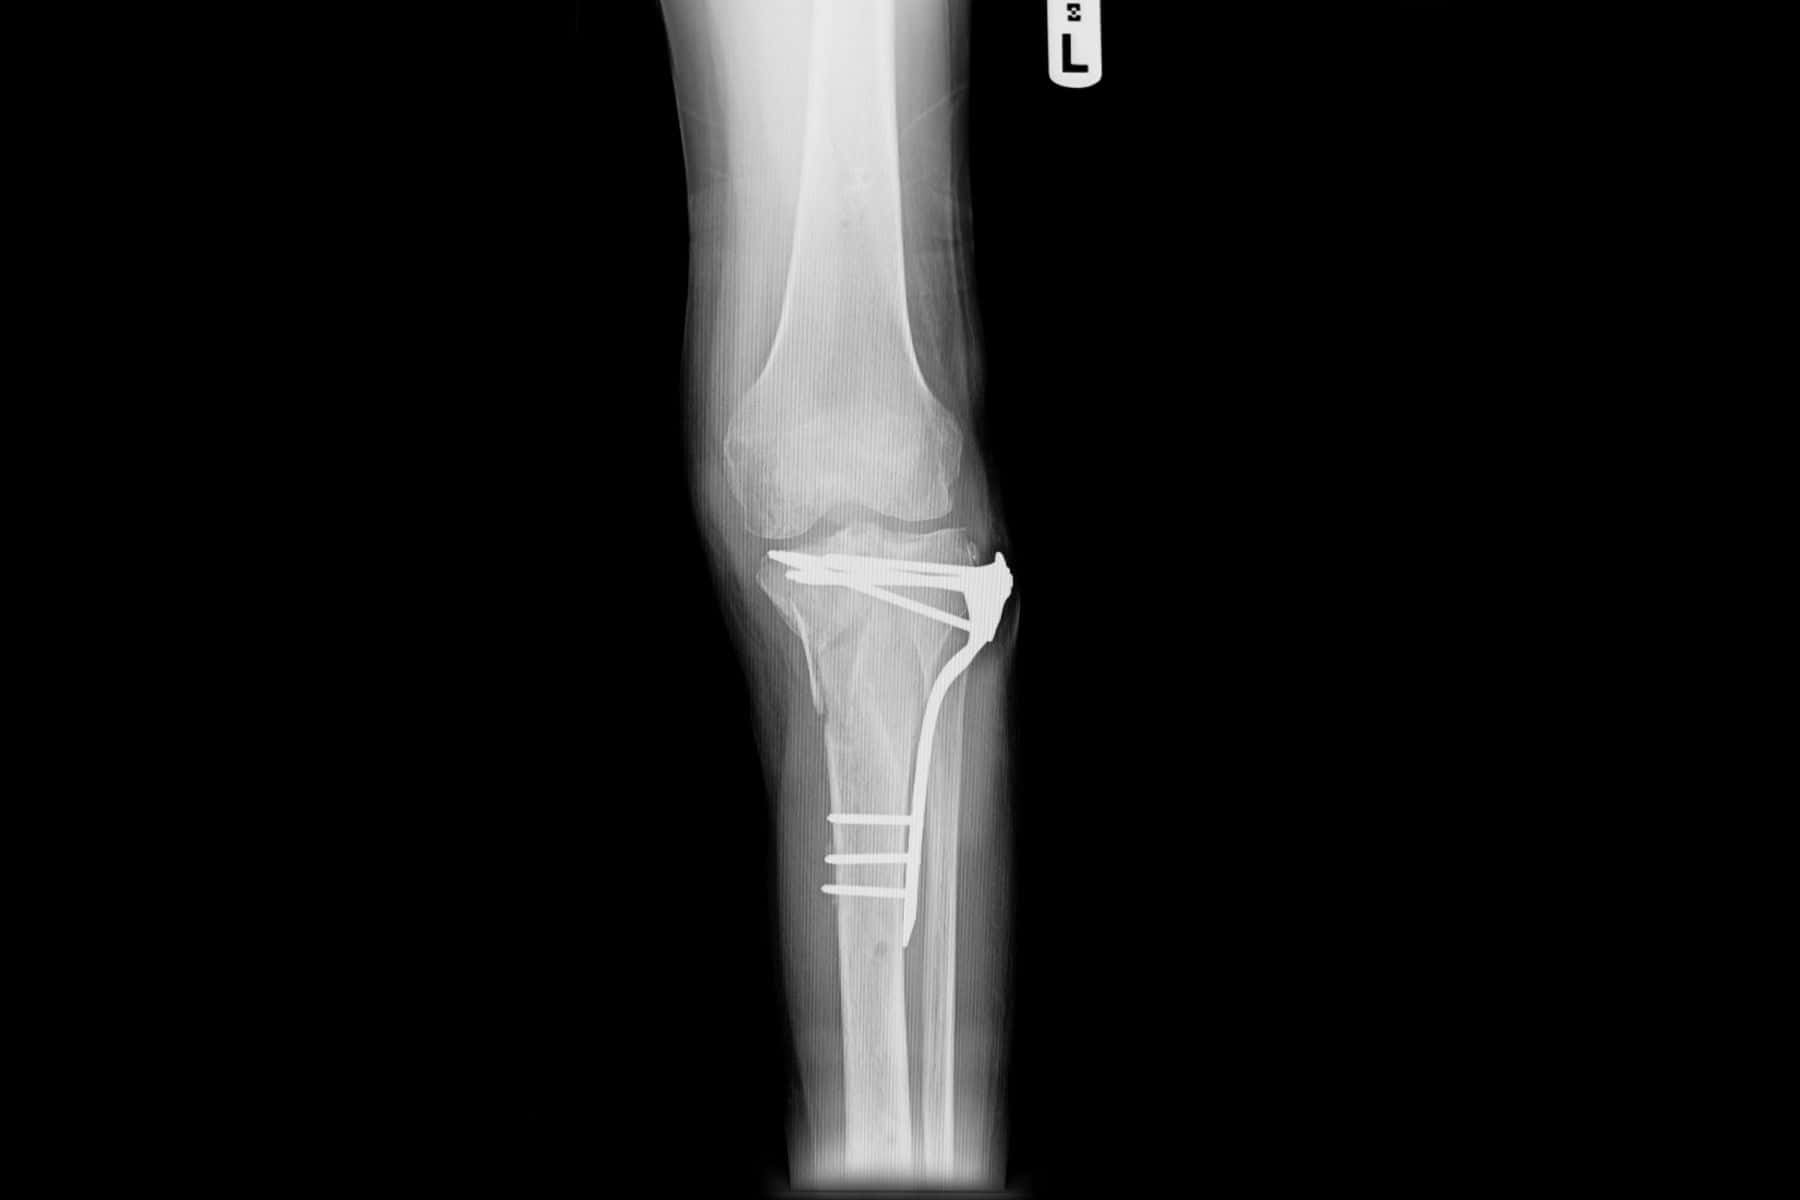

This case study examines the case of an adult female who suffered serious injuries in a golf cart accident. The patient’s accident resulted in intertrochanteric femur fractures and left proximal humerus fractures, requiring open reduction and internal fixation (ORIF).

It is alleged that the orthopedic surgeon selected and implanted improper hardware at the injury site, either due to its size or placement. Two additional surgeries were required for hardware removal and replacement.